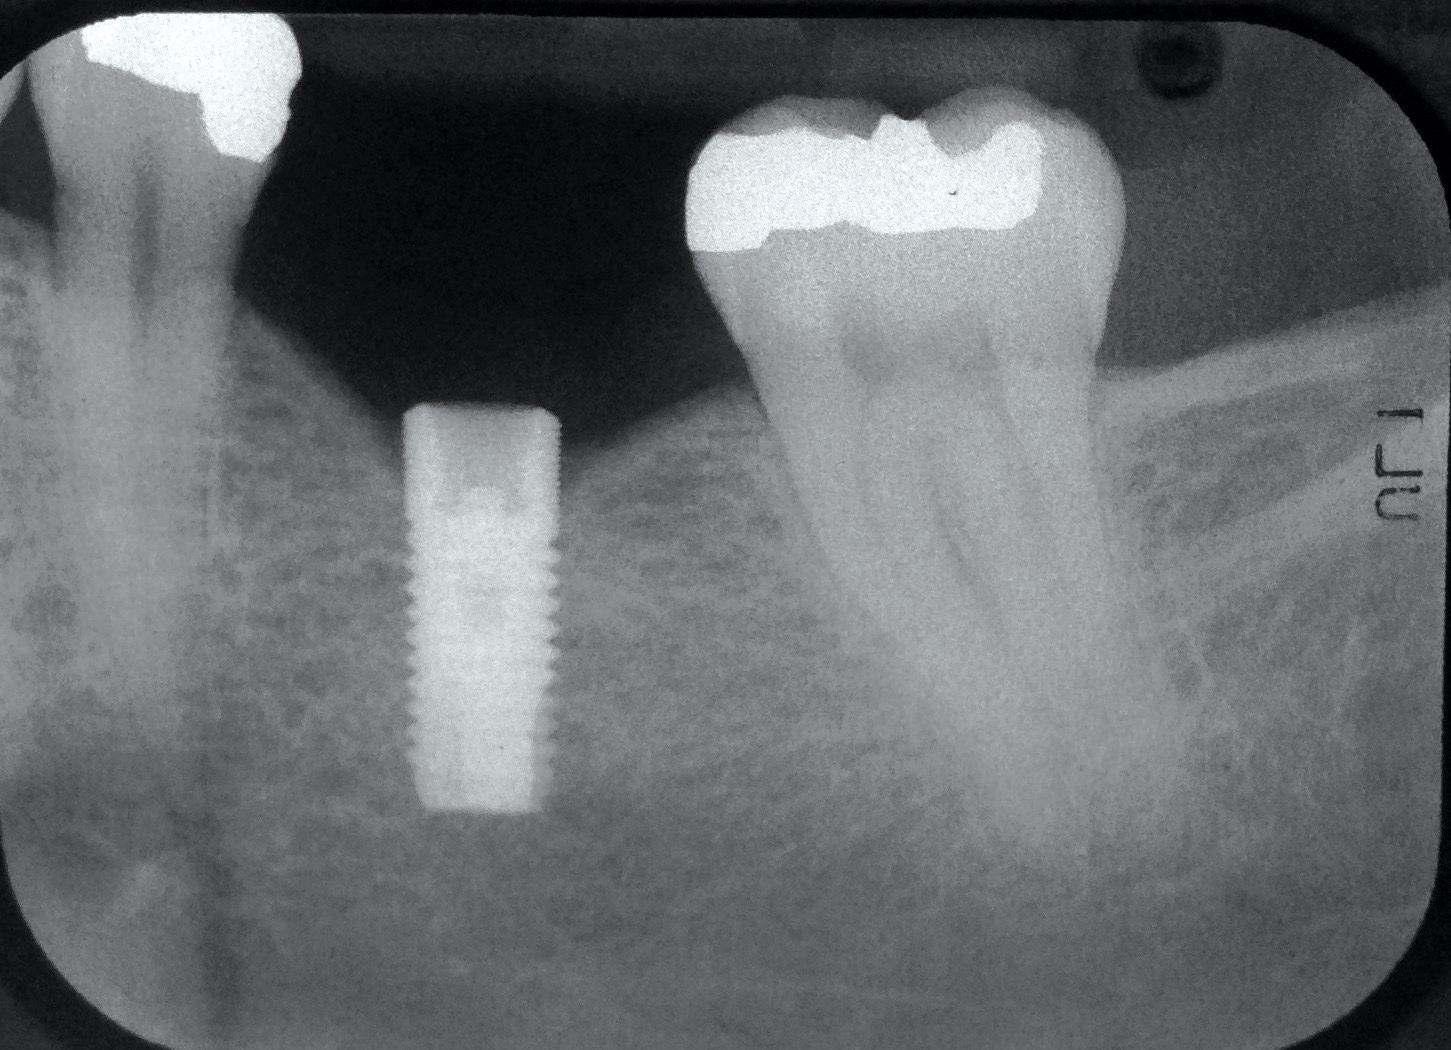

Fig 13. Radiograph depicting peri-implantitis.

Figure 13

Excess Cement Leading to Peri-implantitis

If all implant-supported crowns could be designed for screw retention, no discussion of excess cement would be necessary. However, screw retention is not always possible depending on the location of the access opening and because of the unesthetic appearance in anterior restorations or the mesial/distal angulation of the implant compromising the path of insertion (Figure 12). Residual cement left after crown cementation on implants can lead to peri-implant inflammation, peri-implantitis, and eventual loss of the implant (Figure 13 through Figure 15).25 The presence of lingering excess cement can encourage the development of bacterial colonization and peri-implantitis. Conversely, when too little cement is used, voids in the cement layer can occur and the prosthesis can become loose.26 The deeper the implant crown margin, the more difficult it is to remove excess cement.27

Radiopaque cements that contain zinc phosphate and zinc oxide (with and without eugenol) should be considered to help identify excess interproximal cement; however, this should be used secondarily to proper margin height and careful removal of cement during cementation. Resin cements lack the same opacity as zinc-containing cements and have been shown to be the most difficult to remove.28 Often in the process of removing this excess cement, the abutment surface becomes scratched and damaged, potentiating further plaque accumulation.29